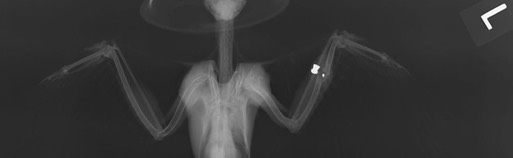

Red-tailed Hawk 18-569

18-569 was found in a field south of Pilot Rock with a suspicious wound on the left elbow. A radiograph showed a badly damaged elbow, small metal fragments, a fractured ulna and damage in the left wrist.

Cooper’s Hawk 18-582

18-582 was found in a yard in a residential area of Othello, WA. He also had a suspicious looking wound on the left elbow. A radiograph showed hairline fractures in the ulna and a badly damaged elbow.